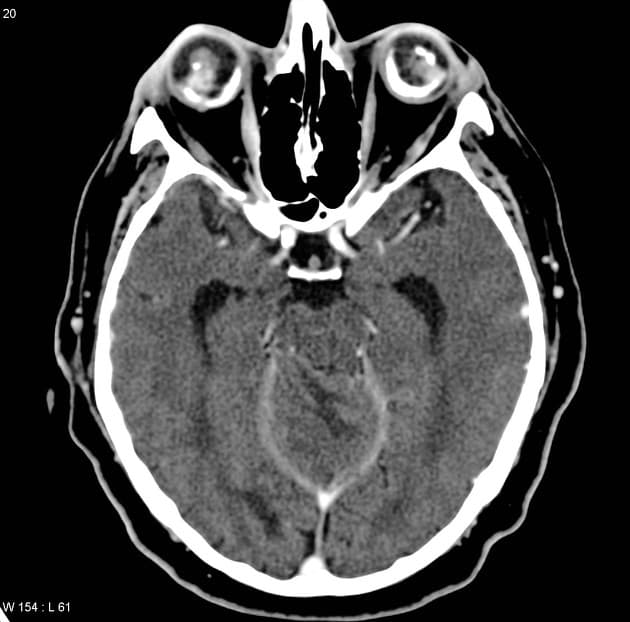

- Não thất bốn bị xóa mờ và có giãn các não thất bên (thấy rõ nhất trên hình ảnh T2 cắt ngang).

- "Chụp cộng hưởng từ thường cho thấy tổn thương tiểu não không tăng quang, tín hiệu tăng trên hình ảnh trọng T2, có hiệu ứng khối và xóa mờ não thất bốn, thường thấy hình ảnh 'sọc hổ' trên cắt ngang."

Bệnh Lhermitte-Duclos, còn gọi là u tăng sản hạch thần kinh tiểu não, là tình trạng tăng trưởng bất thường lành tính của vỏ tiểu não. Đây là dấu hiệu đặc trưng của hội chứng Cowden, một rối loạn trội trên nhiễm sắc thể thường do đột biến gen PTEN, làm tăng nguy cơ u tổ chức nhân và ung thư vú, tuyến giáp, nội mạc tử cung. Hình ảnh học thường rất điển hình: bán cầu tiểu não giãn to lan tỏa, tăng tín hiệu trên trọng T2, không tăng quang, gây hiệu ứng khối và giãn não thất do tắc nghẽn. Hình ảnh 'sọc hổ' trên cộng hưởng từ T2 cắt ngang – do các lá tiểu não xen kẽ tăng và đồng tín hiệu – là đặc hiệu. Chẩn đoán chủ yếu dựa vào hình ảnh học, nhưng sinh thiết có thể cần thiết trong các trường hợp không điển hình. Điều trị bao gồm theo dõi các ung thư liên quan, xử trí triệu chứng và giải áp phẫu thuật nếu có hiệu ứng khối hoặc giãn não thất nặng.